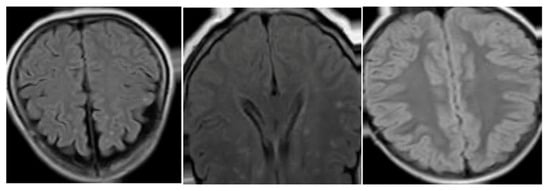

3.1. Dataset

3.1.1. Analysis of Volumes and Slices Dataset

3.1.2. Data Preprocessing